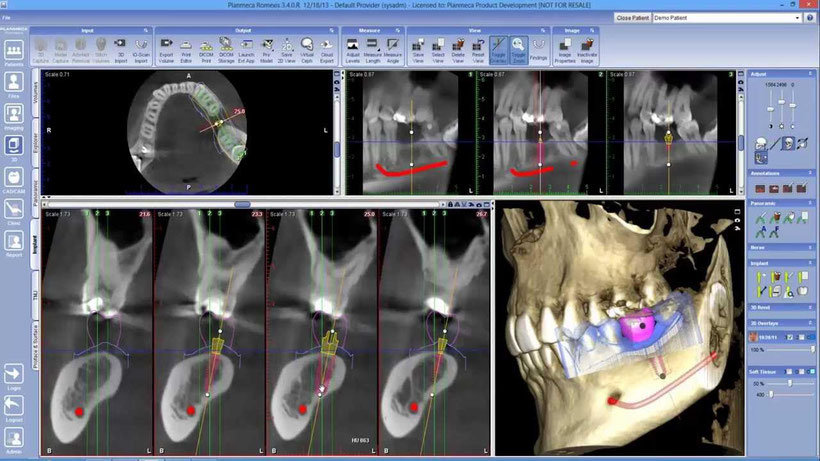

Tomografía CONE BEAM

Es una técnica exploratoria radiográfica de muy baja radiación, que permite obtener imágenes radiológicas detalladas en tres dimensiones de una sección o plano de los maxilares junto a los tejidos blandos y estructuras anexas. Para este procedimiento se usa un tomógrafo CBT/CONE BEAM, cuando el uso de rayos X convencional no es suficiente para abarcar todas las estructuras de interés.

Este tipo de tomografías está indicada para el diagnóstico de trastornos óseos y dentales, como tumores, fracturas, trastornos de la articulación temporo mandibular, procesos infecciosos, etc.

También nos sirven para guiar procedimientos quirúrgicos como planificación de implantes, cirugías mayores y menores.

El especialista le solicitará una tomografía axial computarizada para planificar minuciosamente el tratamiento antes de llevarlo a cabo.

Esta técnica se realiza en un centro especializado en tomografías donde se pedirá al paciente que se mantenga de pie totalmente quieto, mientras coloca su cabeza en el equipo de rayos X y el detector gira alrededor de él en 360°. El paciente no puede llevar ningún tipo de objeto metálico en la cabeza ya que este puede alterar las imágenes de la tomografía, por lo cual deberá retirarse prótesis, joyas etc., durante el procedimiento. La radiación que se emite es mínima para el paciente, sin embargo, está contraindicado en mujeres embarazadas.